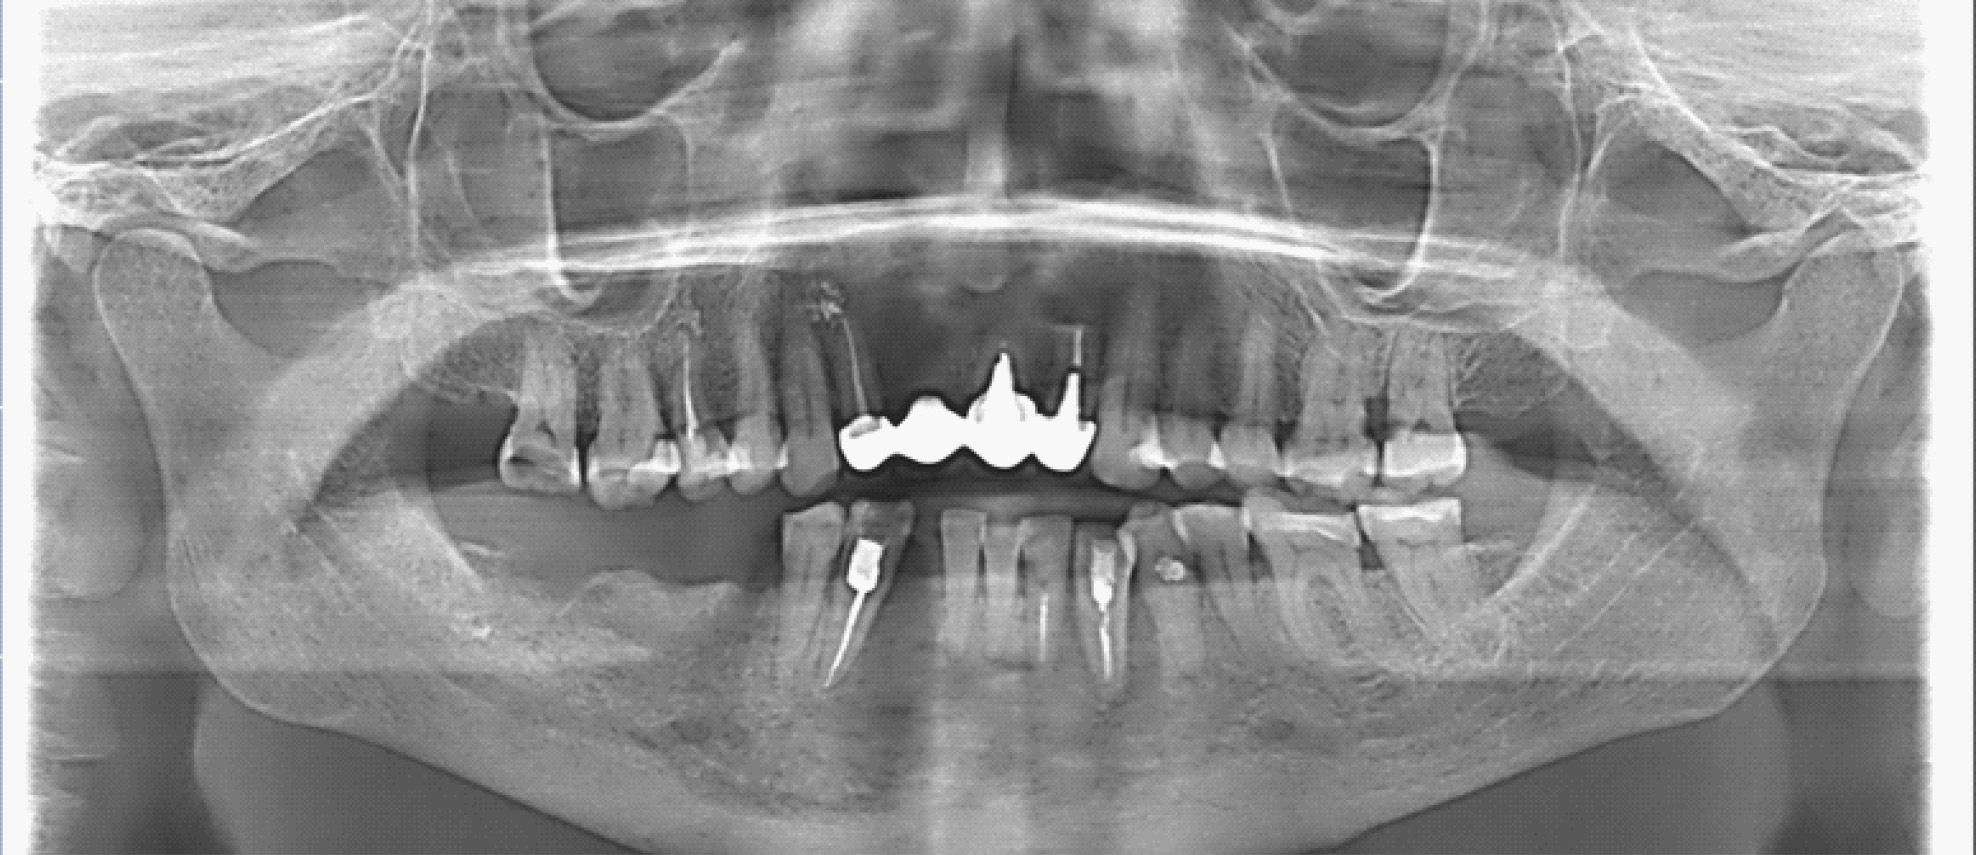

За период лечения пациентки Б. было выполнено хирургическое лечение в следующем объеме: кюретаж лунок удаленных зубов, частичная секвестрэктомия, резекция альвеолярной части нижней челюсти справа, вскрытие и дренирование гнойных очагов в стадии обострения патологического процесса. Отмечалось улучшение клинической и рентгенологической картины в полости рта (рис. 5, 6).

Рис. 6. Ортопантомограмма на этапе лечения остеонекроза нижней челюсти справа у пациентки Б. в 2024 г.